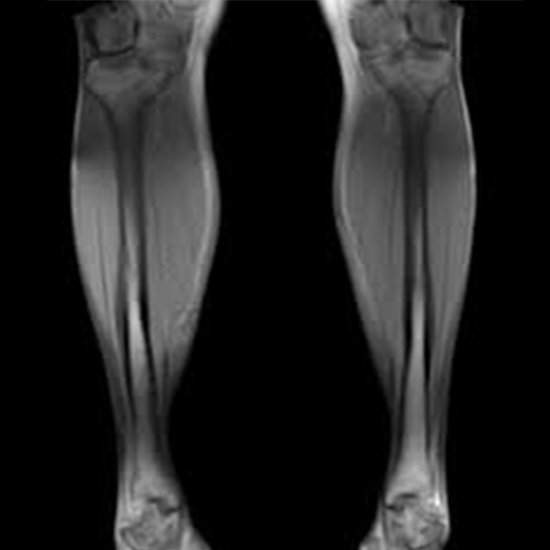

The lower leg's bones, muscles, tendons, ligaments, cartilage, nerves, and blood vessels may be seen in exquisite detail thanks to MRI scans on both legs.

This technique delivers comprehensive images of leg regions that are difficult to determine on CT scans.